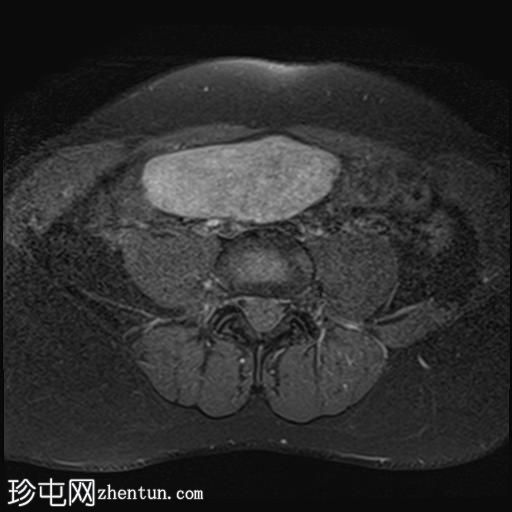

轴位

T2加权像

其中一个位于子宫上方,T2加权像呈中等信号,中心区域呈高信号,增强T1脂肪抑制像未见强化。右侧卵巢增大,增厚的血管蒂扭曲,未见强化,轴位和矢状位T2加权像均显示清晰。

另一个位于子宫后窝,T2加权像呈中等信号,增强扫描显示明显强化。